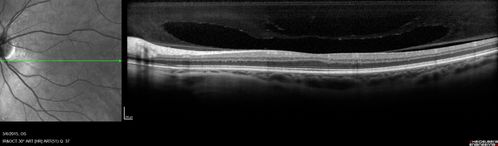

Foveal hypoplasia - aplasia

SD OCT shows persistent plexiform layers in the center of the macula